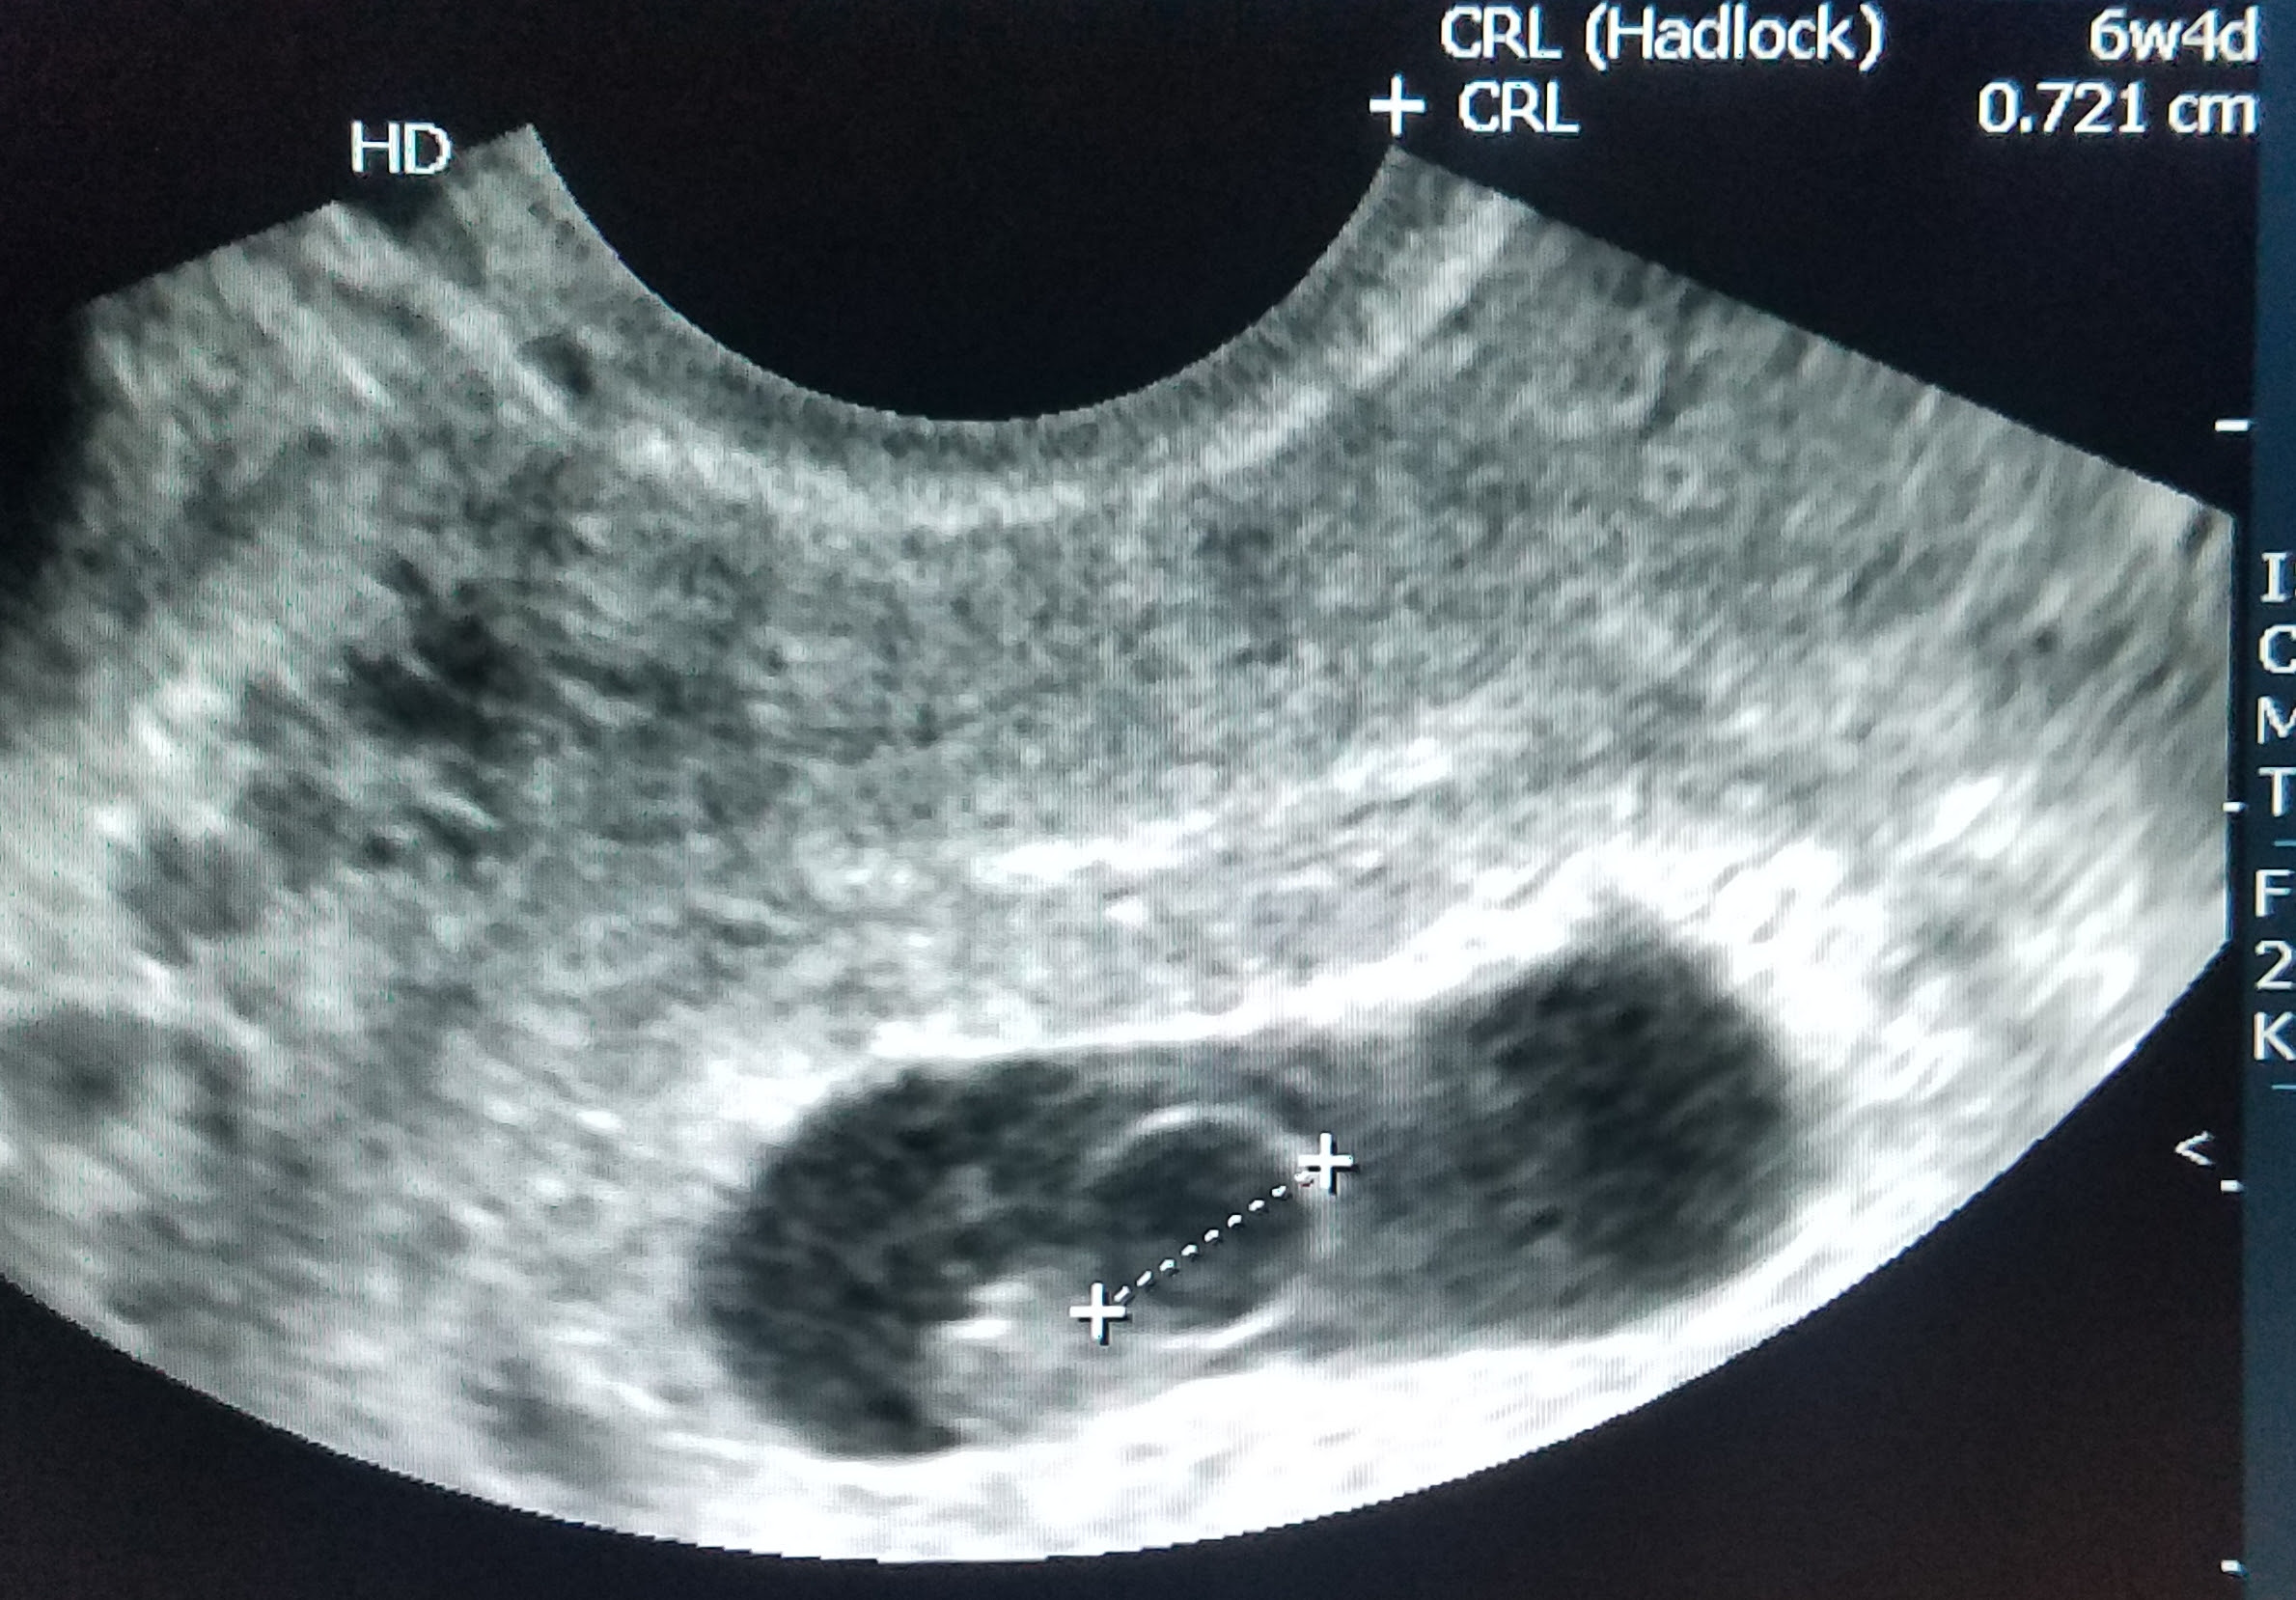

Анализ медицинских данных: желточный мешок и анэмбриония